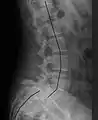

![]() | |

| X-ray of the lateral lumbar spine with a grade III anterolisthesis at the L5-S1 level | |